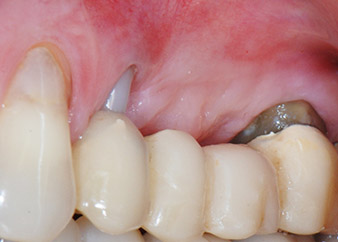

Résultat intermédiaire à deux mois

Les figures 17 et 18 présentent le résultat clinique deux mois après l'intervention chirurgicale. La dent 24 présentait une mobilité réduite, de classe I (Miller) et les tissus mous ne présentaient aucune inflammation. Pour prévenir toute nouvelle infection et pour éviter d'endommager l'attache épithéliale, aucun test n'a été pratiqué à ce stade. Une visite de contrôle a été programmée pour la prochaine incision et la mise en place des parties secondaires de cicatrisation, six mois après l'insertion des implants.

À la consultation des deux mois, la mobilité de l'« élément dentaire » 24 restant était déjà passée de Miller 2 à Miller 1. L'attache des tissus mous était au niveau de la dent voisine 23. De plus, en l'absence de symptômes endodontaux ou parodontaux, son pronostic devra peut-être être révisé.